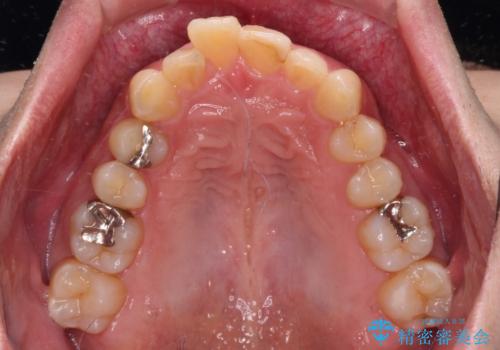

深い咬み合わせで顎が疲れる ワイヤー矯正でディープバイトを解消

- 深い咬み合わせによる食いしばりで、顎関節や頭が痛むことがあるとのことで来院された患者様です。

歯ぎしりができないくらい強い食いしばりの咬合状態であったため、奥歯の歯軸を起き上がらせることで咬合を挙上させ、歯ぎしりができるようにしていくこととしました。

下顎が左側にずれているため、上下正中は最大限合わせられるところまで合わせるゴールとなりました。